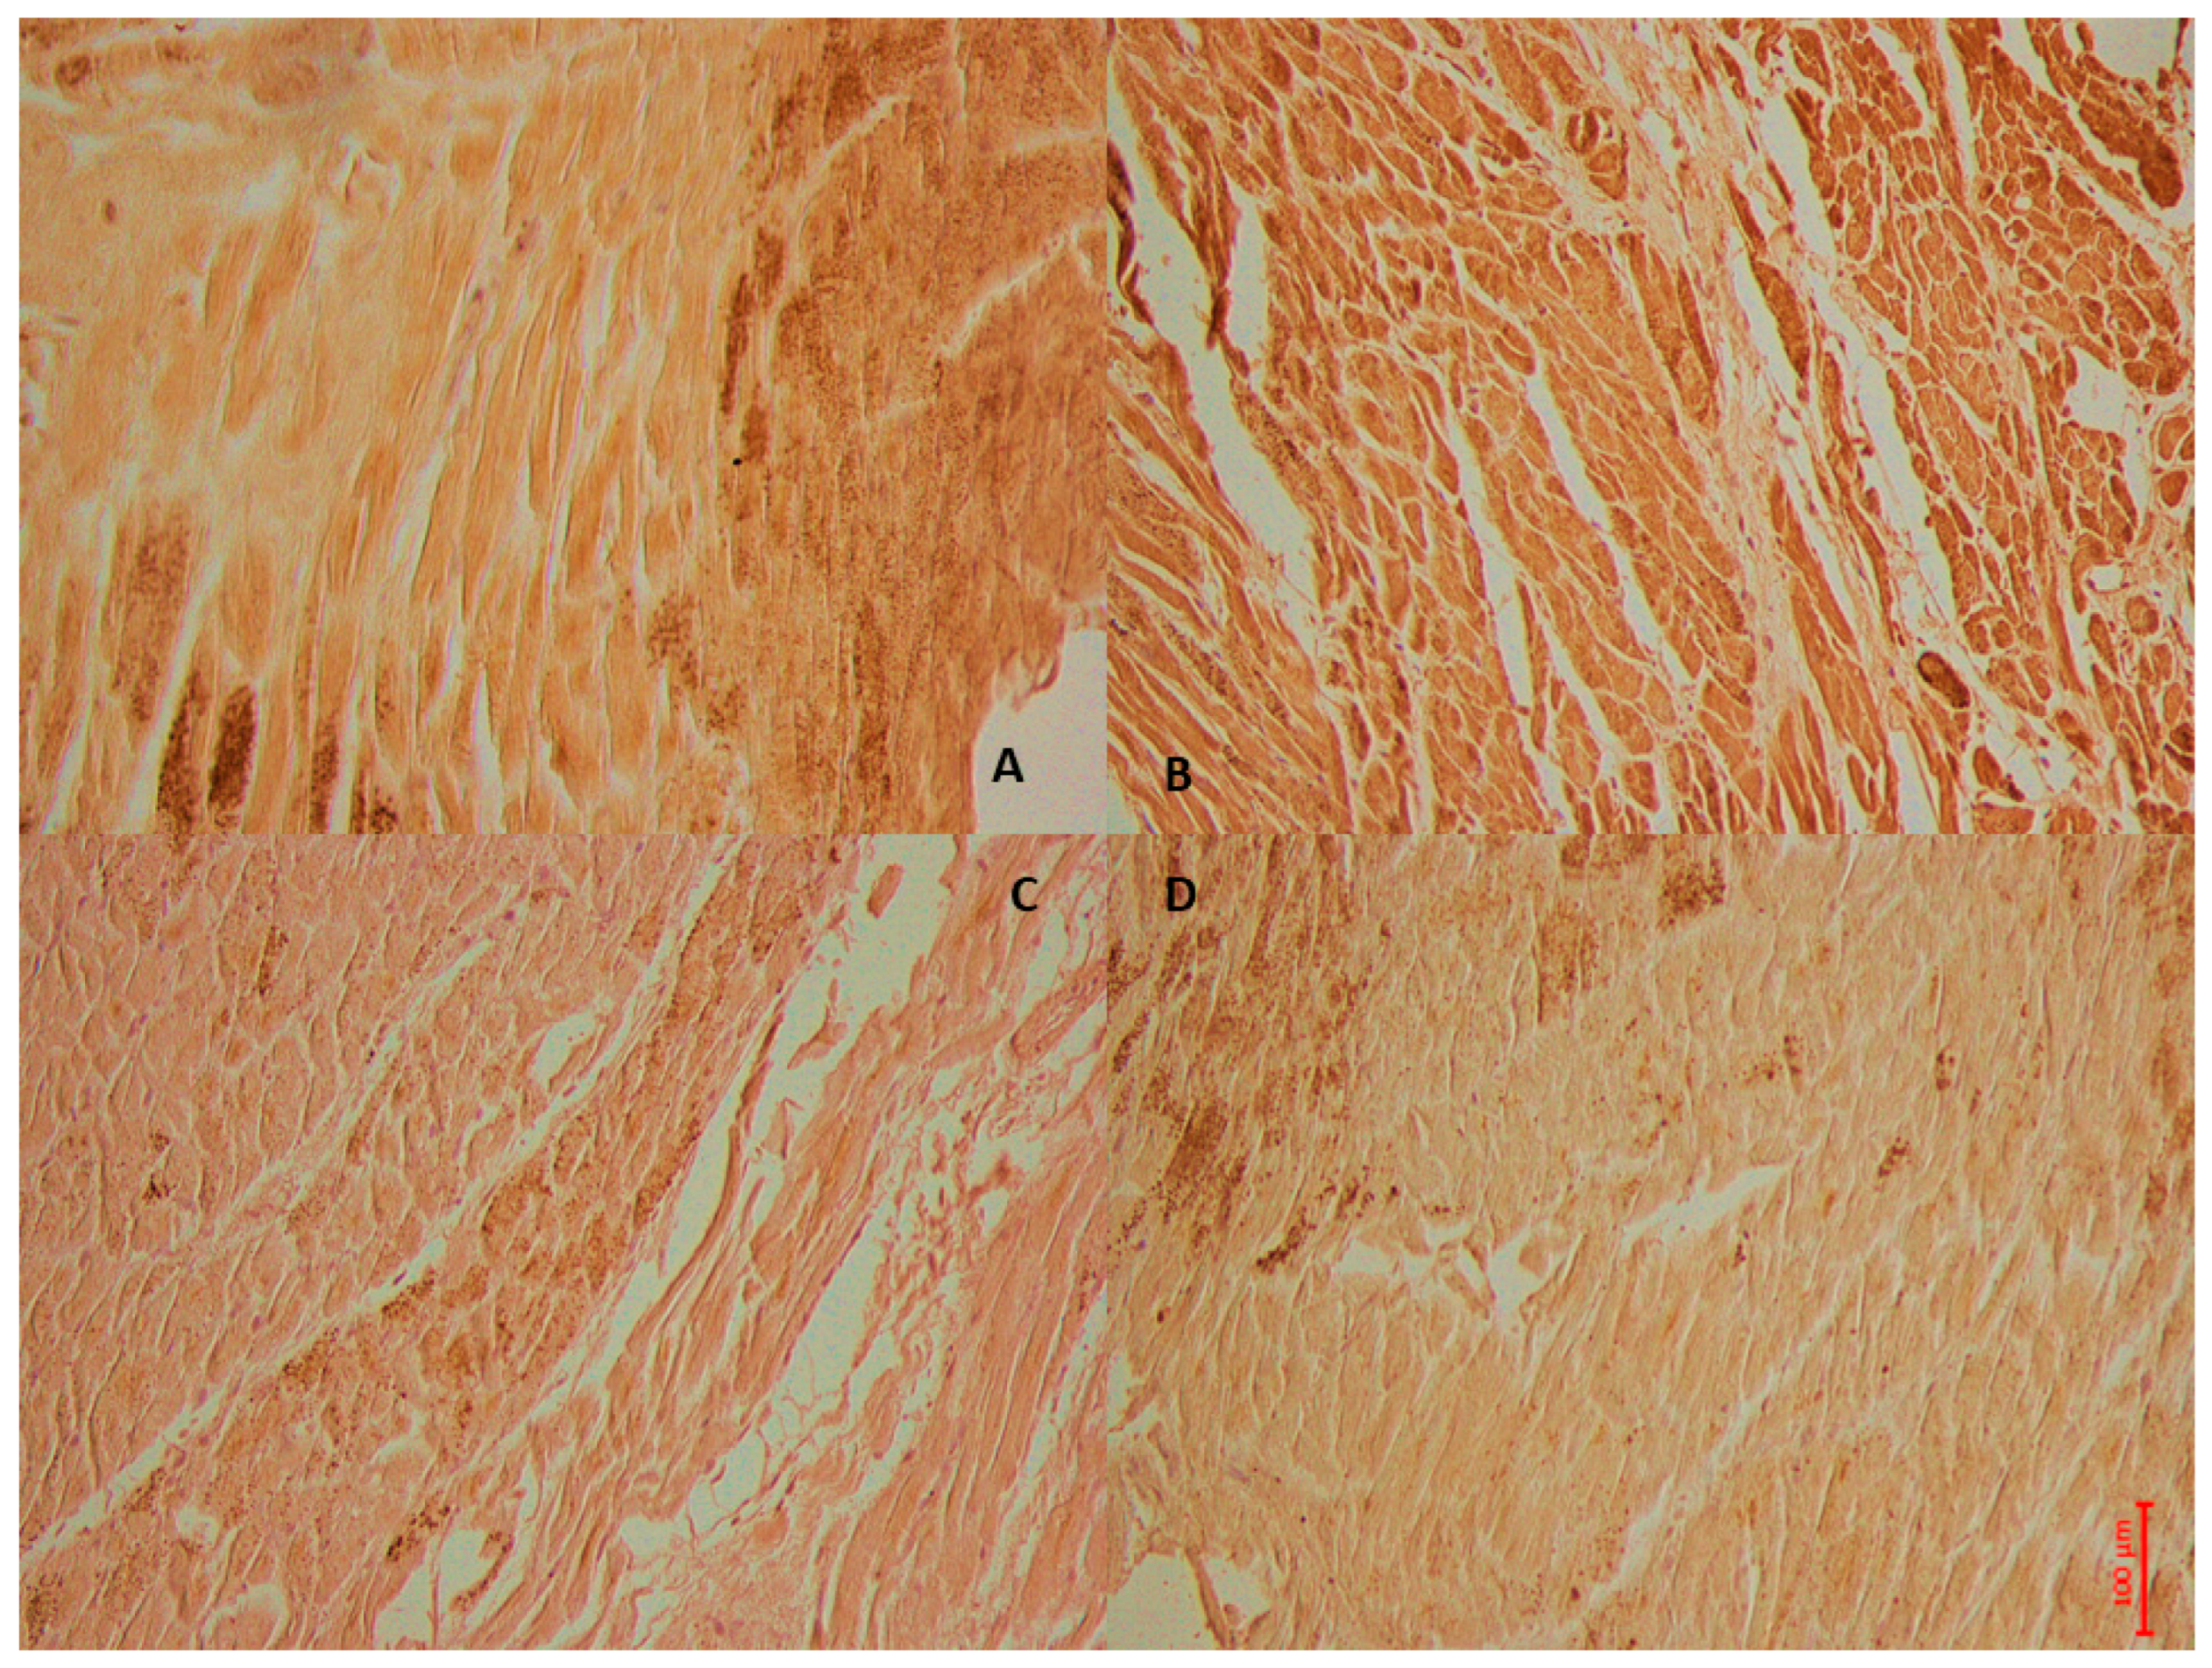

- Tossetta, G.; Fantone, S.; Compagnucci, P.; Marzioni, D.; Montanari, E.; Neri, M.; Busardò, F.P.; Montana, A. γ-H2AX: A useful tool to detect DNA damage in sudden cardiac death heart tissues, an experimental study. Tissue Cell 2025, 96, 103042. [Google Scholar] [CrossRef]